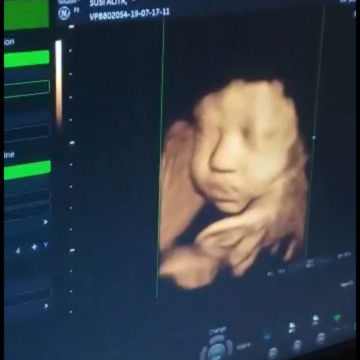

foto USG 36week

Haii bun..ada yg ngerasain sama kaya aku gak ya,pengen usg cm buat liat wajah si calon debay buat obat kangen? #Ini wajah papanya banget apalagi itu idungnya ?

Iyaaa bun.. kmrin usg itu pas 36week bun.skrg uda 37 week

Itu yg 4d ya bund... Brp week bund